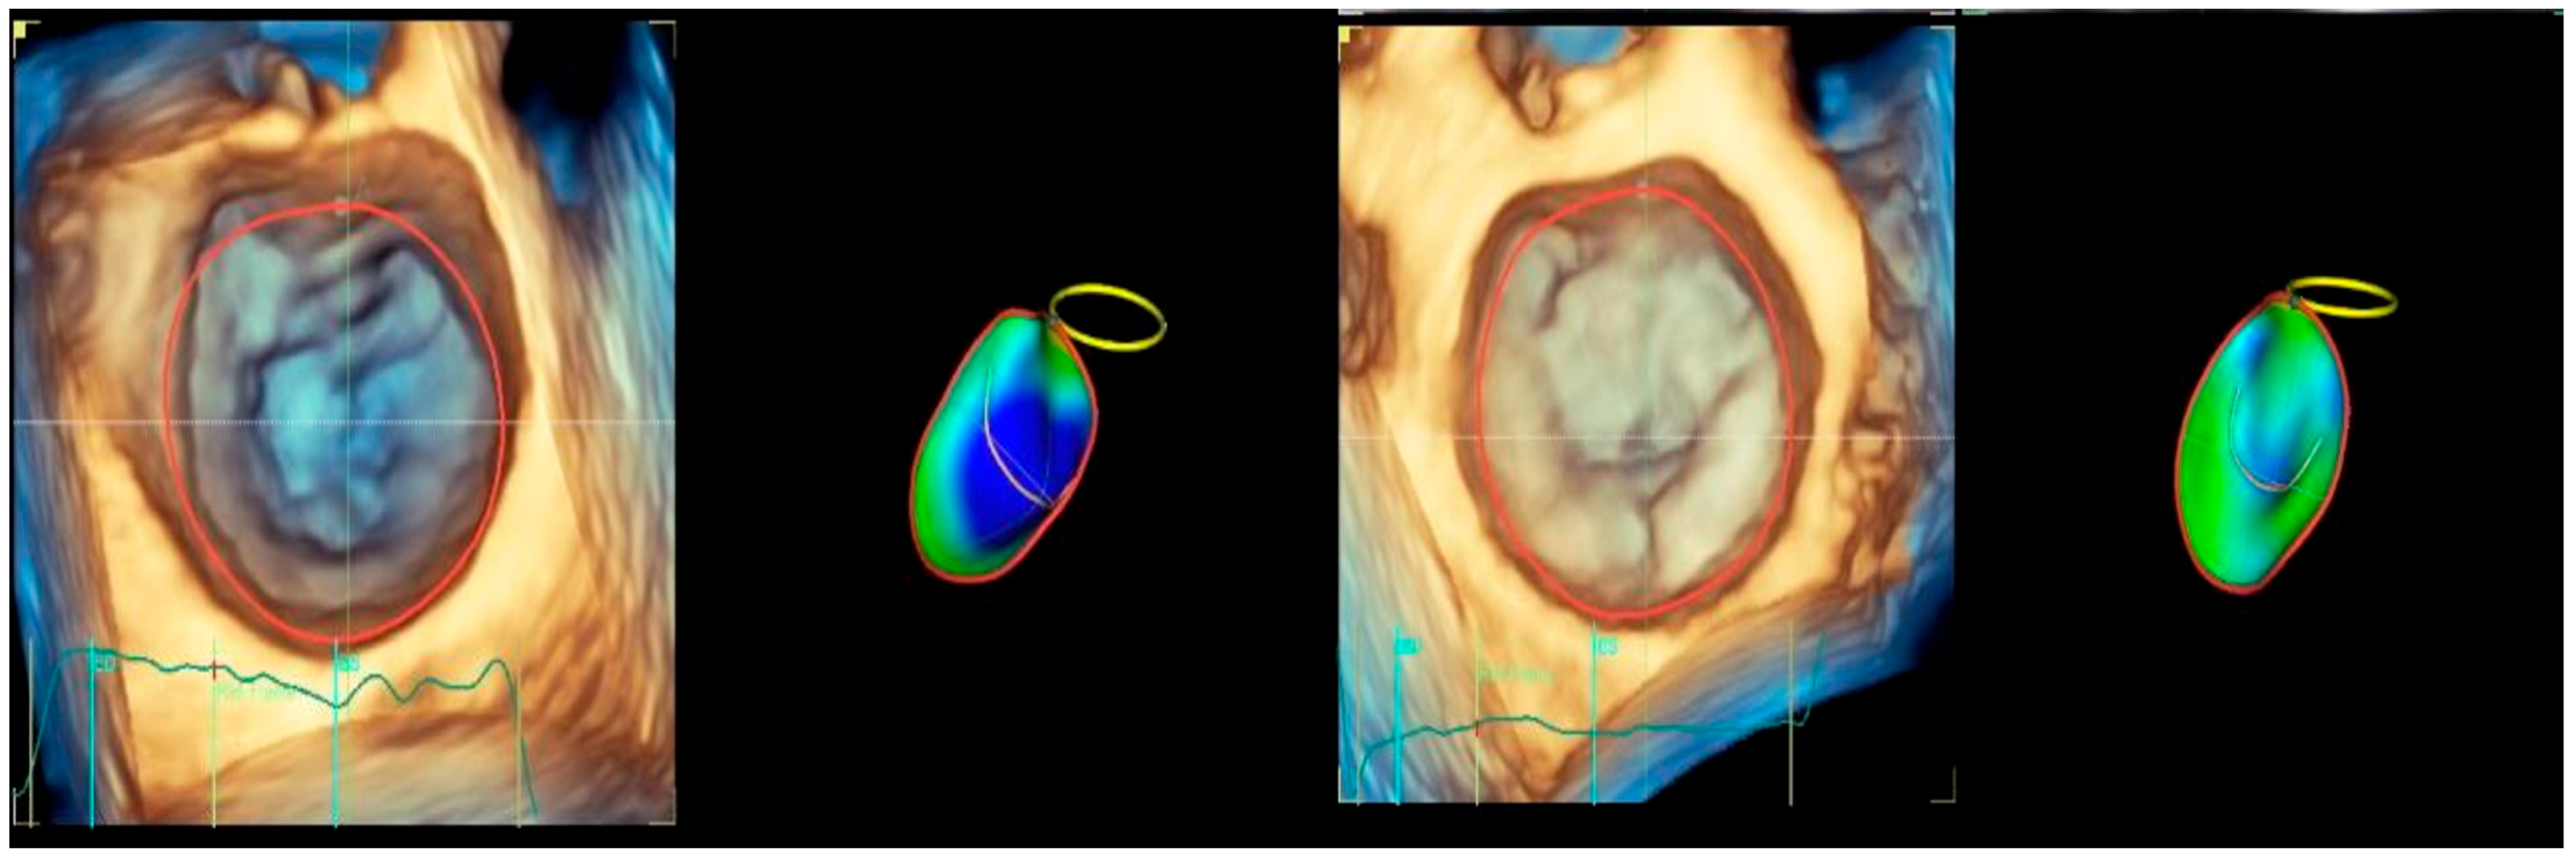

For the LA quantification, the landmark was located in the center of the MV at the annulus level in the three planes (Figure 2). The segmentation algorithm computes the deformation of the model. For LAS longitudinal and circumferential strain evaluation, the ‘review’ function was selected. The software automatically detected the endocardial border in three-dimensional space throughout the cardiac cycle. Care was taken to ensure correct delineation by rotating along the long axis of the LA. The investigator manually adjusted the border at end-diastole (Figure 2A), end-systole (Figure 2B), and pre-atrial contraction (Figure 2C) to include the entire atrium and exclude the pulmonary veins and LA appendage. The software automatically generated all left atrium parameters, including the LAS (Figure 3) [19].

Figure 2.

Left atrium segmentation: (A) MV center identification; (B) left atrium endocardial border in three-dimensional spaces during diastole; (C) left atrium endocardial border in three-dimensional spaces during systole; (D) left atrium endocardial border in three-dimensional spaces before atrial contraction.

Figure 3.

Left atrium parameters provided by Four-Dimensional Auto Left Atrial Quantification (4D Auto LAQ) software, including left atrium reservoir strain.

The definition of the LA cycle was R-R gating, in which the LA cycle is defined from the peak of the R-wave to the same point of the next cycle. The method presented the LA strain as a monophasic curve (Figure 3). The advantage of the R-R gating method is its availability even during AF [20]. The reference point was set at the left ventricle ED. During the reservoir phase, the LA wall lengthened, and the strain had a positive value. In the other 2 phases, the LA wall shortened, and the strains had negative values. LA longitudinal strain parameters obtained using this technique included LA reservoir strain (LASr), LA conduit strain (LAScd), and LA contraction strain (LASct), and LA circumferential strain parameters included the LA reservoir circumferential strain (LASr-c), LA conduit circumferential strain (LAScd-c), and LA contraction circumferential strain (LASct-c). The studies showed that the total function of the LA was best reflected by reservoir strain [21,22]. From all the 4D LA parameters presented by the software, this parameter was used for the LA function evaluation.